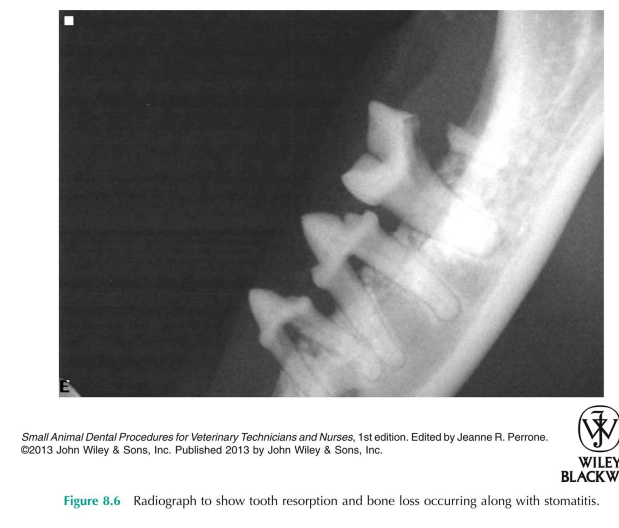

stomatitis